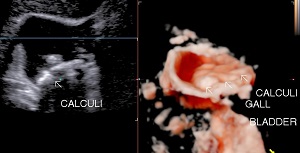

• Cholelithiasis: Presence of calculus/ calculi in gall bladder with normal wall thickness is known as cholelithiasis.

• Findings: Shows presence of calculi in gall bladder/ common bile duct, its mobility & complications.

• Solitary Calculi:

• Multiple Calculi